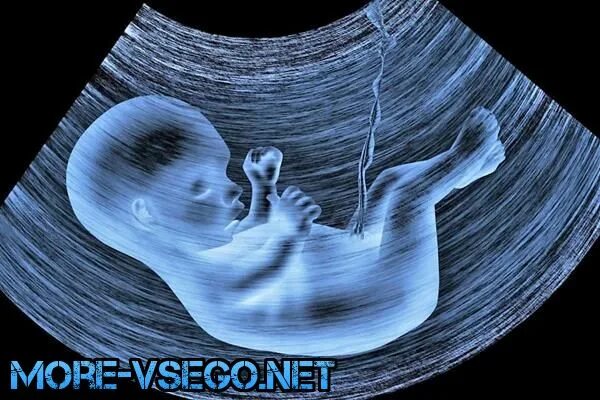

14 неделя ощущение